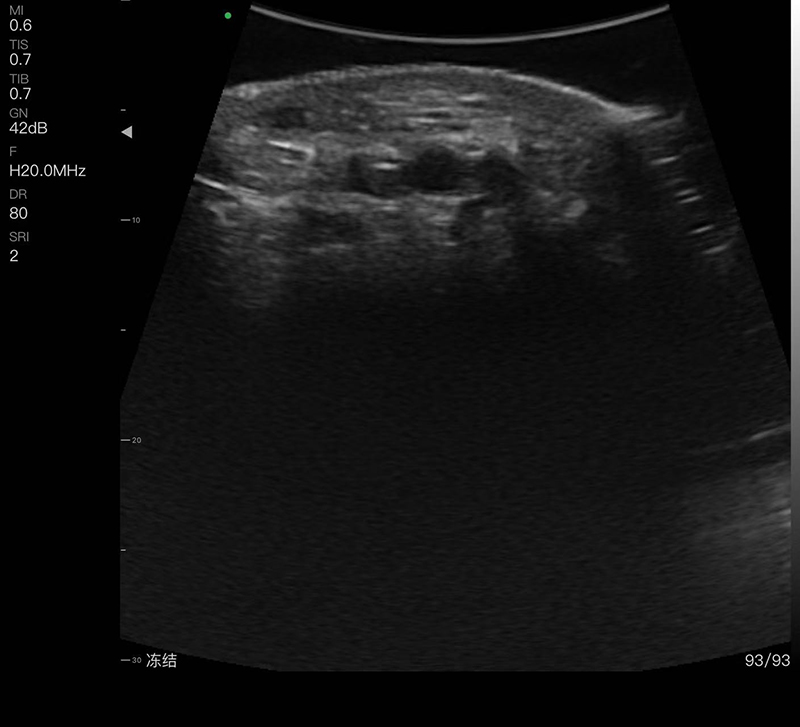

带指套探头的掌上彩超,小小的掌超主机放在口袋可随处走,手指套着探头即可完成打图成像,让手不再需要握着探头而可解放出来还能拿其他东西,特别适合术中等应用

- 探头频率:16/20MHz

- 扫描深度:10/20/30/40mm,可调

- 显示模式:B、B/M、COLOR、PDI、PW